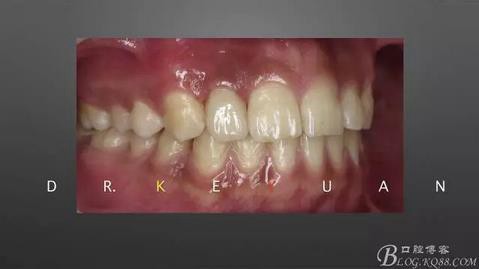

7、最終爭取了2周的時(shí)間,能看到牙齦有明顯的改善

360截圖20170120135245605.jpg

8、排齦、硅橡膠第二次取模制作氧化鋯全瓷冠

360截圖20170120135253669.jpg

9、完成最終修復(fù)體

10、復(fù)診試戴最終修復(fù)體(又爭取了2周的時(shí)間,再加上技師對最終修復(fù)體鄰接關(guān)系的設(shè)計(jì),牙齦恢復(fù)效果明顯)